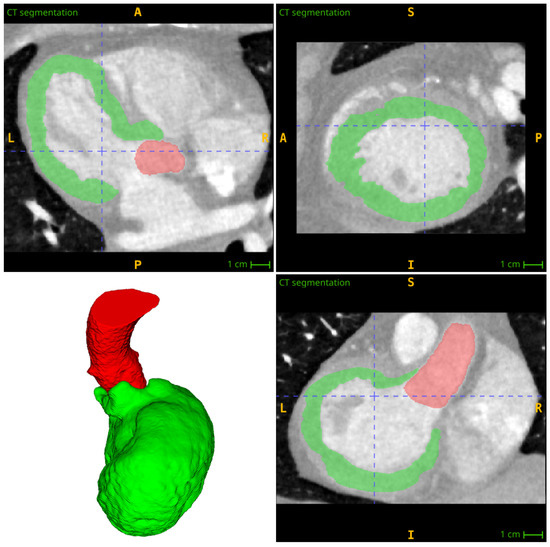

In step 5, the ventricular wall is divided into individualized zones. Each zone is prescribed to a specific part of a previously constructed 1D coronary tree. Starting from the virtual root connecting the left and right coronary branches, the 1D network is then processed recursively. The ventricular wall is divided into several zones and the descending bifurcations are processed at each bifurcation point. Finally, the entire wall of the myocardium is divided into individual zones that correspond to the terminal arteries.

In this approach to the subdivision of a wall, the distance from the coronary arteries is taken into account. At the initial point of branching of the coronary artery, the artery is divided into two parts. The distances between each segment of the coronary arteries and each ventricular voxel are then calculated. These distances are then used to assign the voxels to the branch with the minimum distance by constructing zones where the distance to the selected branch is less than the distance to other branches.

The myocardial wall is divided into individual zones corresponding to the coronary segments by recursively descending through the coronary tree. As this process is carried out, the ventricle is partitioned, with only the part already belonging to the parent branch being taken. This is conducted in the same way at each branching point until the partitioned myocardial wall corresponding to the terminal segments of the coronary tree has been obtained (Figure 3).

Figure 3. Final partitioning of the left ventricle wall with supplying coronary arteries (the same color as a segment) and aorta (shown in red).